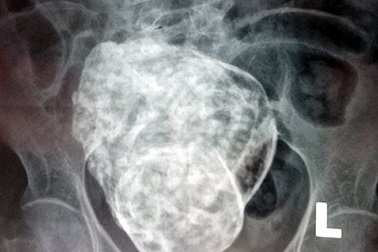

Viên sỏi “khủng” nằm trong thận của bệnh nhân bị thận móng ngựaMột viên sỏi nằm trong thận của một bệnh nhân ở Hà Tĩnh có kích thước “khủng” lên tới 69,34mm x 52,04mm vừa được các bác sĩ Bệnh viện Đa khoa Hà Tĩnh thực hiện phẫu thuật thành công.